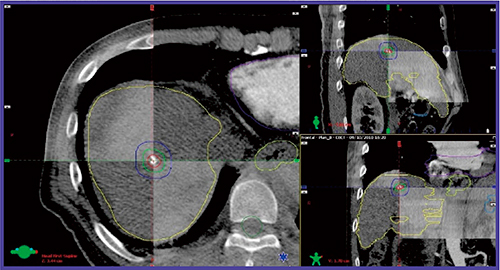

当院では,肝臓に対するSBRTにおける呼吸性移動制御の第一選択は,「abches」(エイペックスメディカル社製)を使用した安静時呼気停止である。これは,われわれの過去の研究1)で報告したが,安静時呼吸停止のintrafractional errorは呼気時の方が吸気時に比べて小さいためである。位置照合においては近年,kV imagingやcone beam CT(CBCT)などのIGRT(image guided radiotherapy)システムが普及しており,肺腫瘍の位置確認は比較的容易に可能だが,肝臓では組織間コントラストに乏しいため,腫瘍の位置確認が困難である。当院では,SBRT前に肝動脈化学塞栓術(TACE)を行う場合が多く,集積するリピオドールがSBRTの際にも残存しているため,リピオドールの位置を腫瘍の位置とみなしCBCTで位置照合を行っている(図1)。リピオドールが残存しない場合,横隔膜面を基準とした位置照合を行っている。過去の研究において,われわれは横隔膜面照合および骨照合を行った場合のリピオドールの位置誤差を解析した2)。図2に結果を示すが,骨照合より横隔膜面照合を行った方が位置誤差は小さいことがわかる。われわれは,この解析により各照合法に必要なセットアップマージンを算出して,ターゲットの線量を担保している。

図1 肝臓癌SBRTにおけるCBCTによるIGRTの例

治療計画CTとCBCT画像を重ね合わせ,位置ズレの有無を確認している。